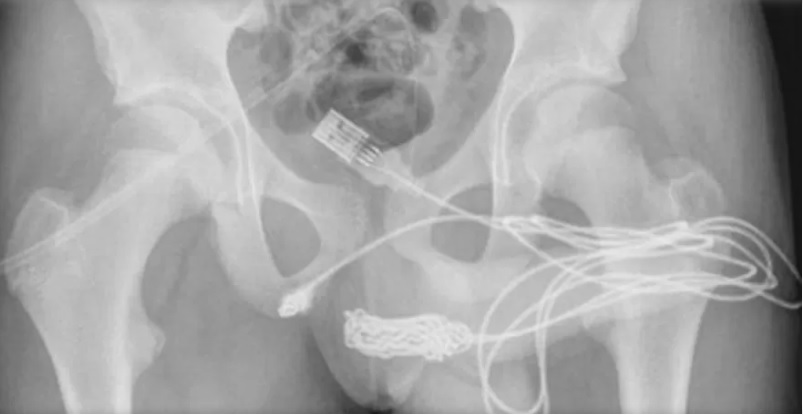

Segundo os relatos do garoto, ele entrou em pânico quando percebeu que o cabo havia ficado preso dentro do órgão, causando fortes dores. De acordo com o tabloide inglês Daily Star, o adolescente foi levado ao hospital e passou por uma radiografia, que mostrou a gravidade da situação.

O cabo não apenas ficou preso na parte interna do pênis, como também fez alguns nós e ficou emaranhado na uretra. Os médicos responsáveis pelo tratamento relataram o incidente e a extração do objeto do corpo do paciente em um relatório, divulgado no Science Direct.

"O paciente era um adolescente saudável e em boa forma, sem histórico de distúrbios de saúde mental. As duas pontas do fio USB estavam saindo do meato uretral externo, enquanto a parte do meio do fio permanecia dentro da uretra", escreveram.